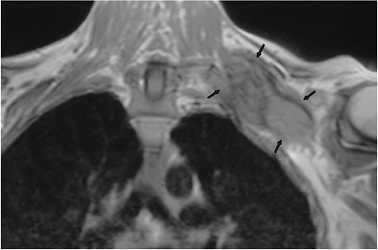

P.511

FIGURE 7-50 Metastatic tumor involving the brachial plexus. Coronal T1-weighted image demonstrates a large mass (arrows) encasing the brachial plexus.